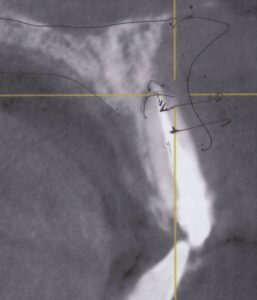

インビザラインで失敗した45歳女性

骨から歯が飛び出ている

Invisalign correction failure

奥歯が噛んでいない

初期診断やシミュレーションの精度不足

歯根の動きや骨の状態の個人差を見誤った